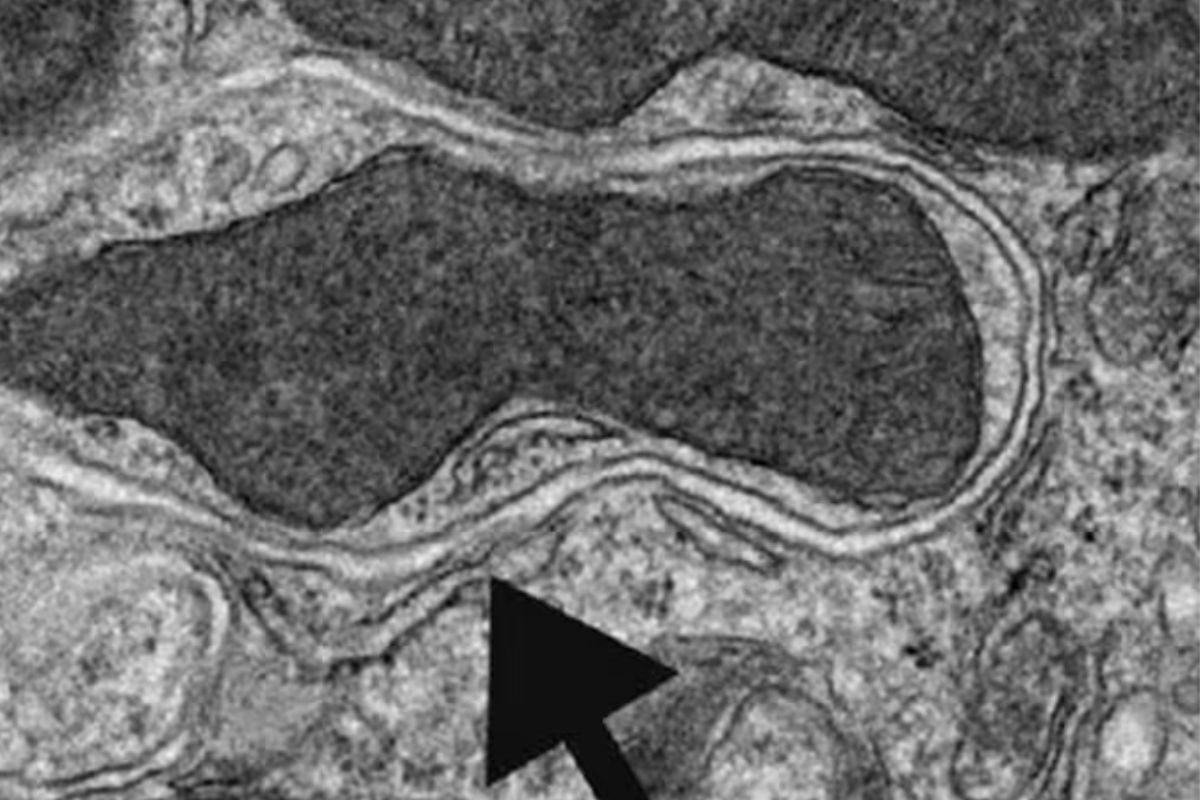

La autofagia es un sistema de “limpieza interna” que activa el propio cuerpo para eliminar residuos celulares, proteínas defectuosas y estructuras dañadas. En términos simples, las células se “comen” lo que ya no sirve para reutilizarlo como energía o materia prima, favoreciendo su correcto funcionamiento.